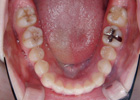

歯を抜いて治療した例 その1

治療前

治療途中

治療後